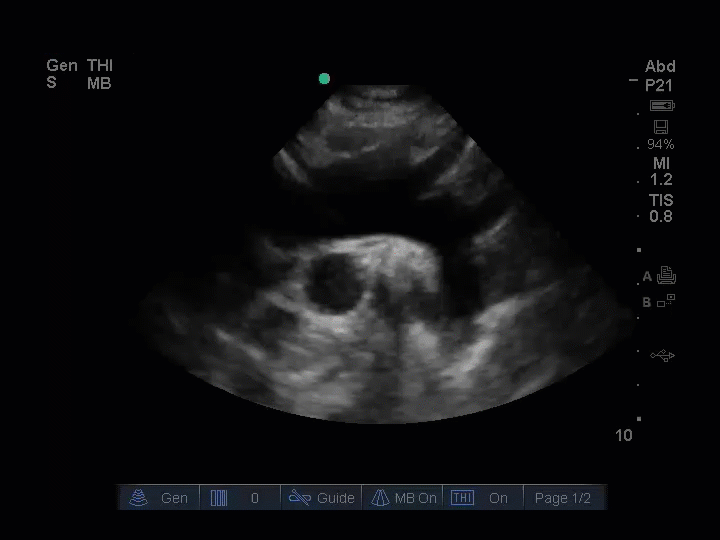

The patient was intubated, and a POCUS echocardiogram was performed. The parasternal long axis view identified a dilated aortic root, measuring 5cm. (Img. 1) This finding prompted EPs to ultrasound the aortic arch, the carotid arteries, and the abdominal aorta in search of dissection flaps. Dissection flaps were visualized in the aortic arch and in the right common carotid artery. The descending abdominal aorta could not be visualized due to bowel gas conditions, likely related to bag-valve-mask therapy in route. A cardiothoracic surgeon was consulted immediately and met the patient at the CT scanner within minutes of her arrival.

(Img. 1) PSLAX aortic root ~5cm. (Img. 2) Normal aortic root appearance.

Echo Window: Parasternal long axis view (PSLAX)

The PSLAX view of the heart is a standard echocardiographic window used in EUS. The aortic root is identified at the basilar center of the heart, imaging well in this view. (Img. 2) The PSLAX is performed by placing the transducer over the long axis of the heart, in the 3rd-5th parasternal rib space. The aortic outflow tract is visualized exiting the heart superiorly between the two neighboring basilar structures, the right ventricular outflow tract (RVOT) and the left atrium (LA) (Img. 2). A normal aortic outflow tract measures < 3.8 cm (12) and appears similar in diameter to the RVOT and the LA by comparison. (Img. 2) When the aortic outflow tract grossly appears to be the largest of the three basilar structures of the heart (Img. 1), the presence of thoracic aneurysm is considered, and the aortic root is scanned thoroughly for visualization of an intimal flap. Intimal flaps appear as an undulating echogenic (white) line within the lumen of the aorta. When present, intimal flaps can be visualized in both the long and short axis views of the aortic root as demonstrated in this 71-year-old patient with anterior chest pain and posterior interscapular pain. (Vid. 1) When imaging the aortic root, cautious interpretation is required to avoid mistaking the motion of the aortic valve leaflets as dissection flaps. In our stroke patient, the aortic root was approximately 5cm in diameter and no intimal flap was identified. (Vid. 2)